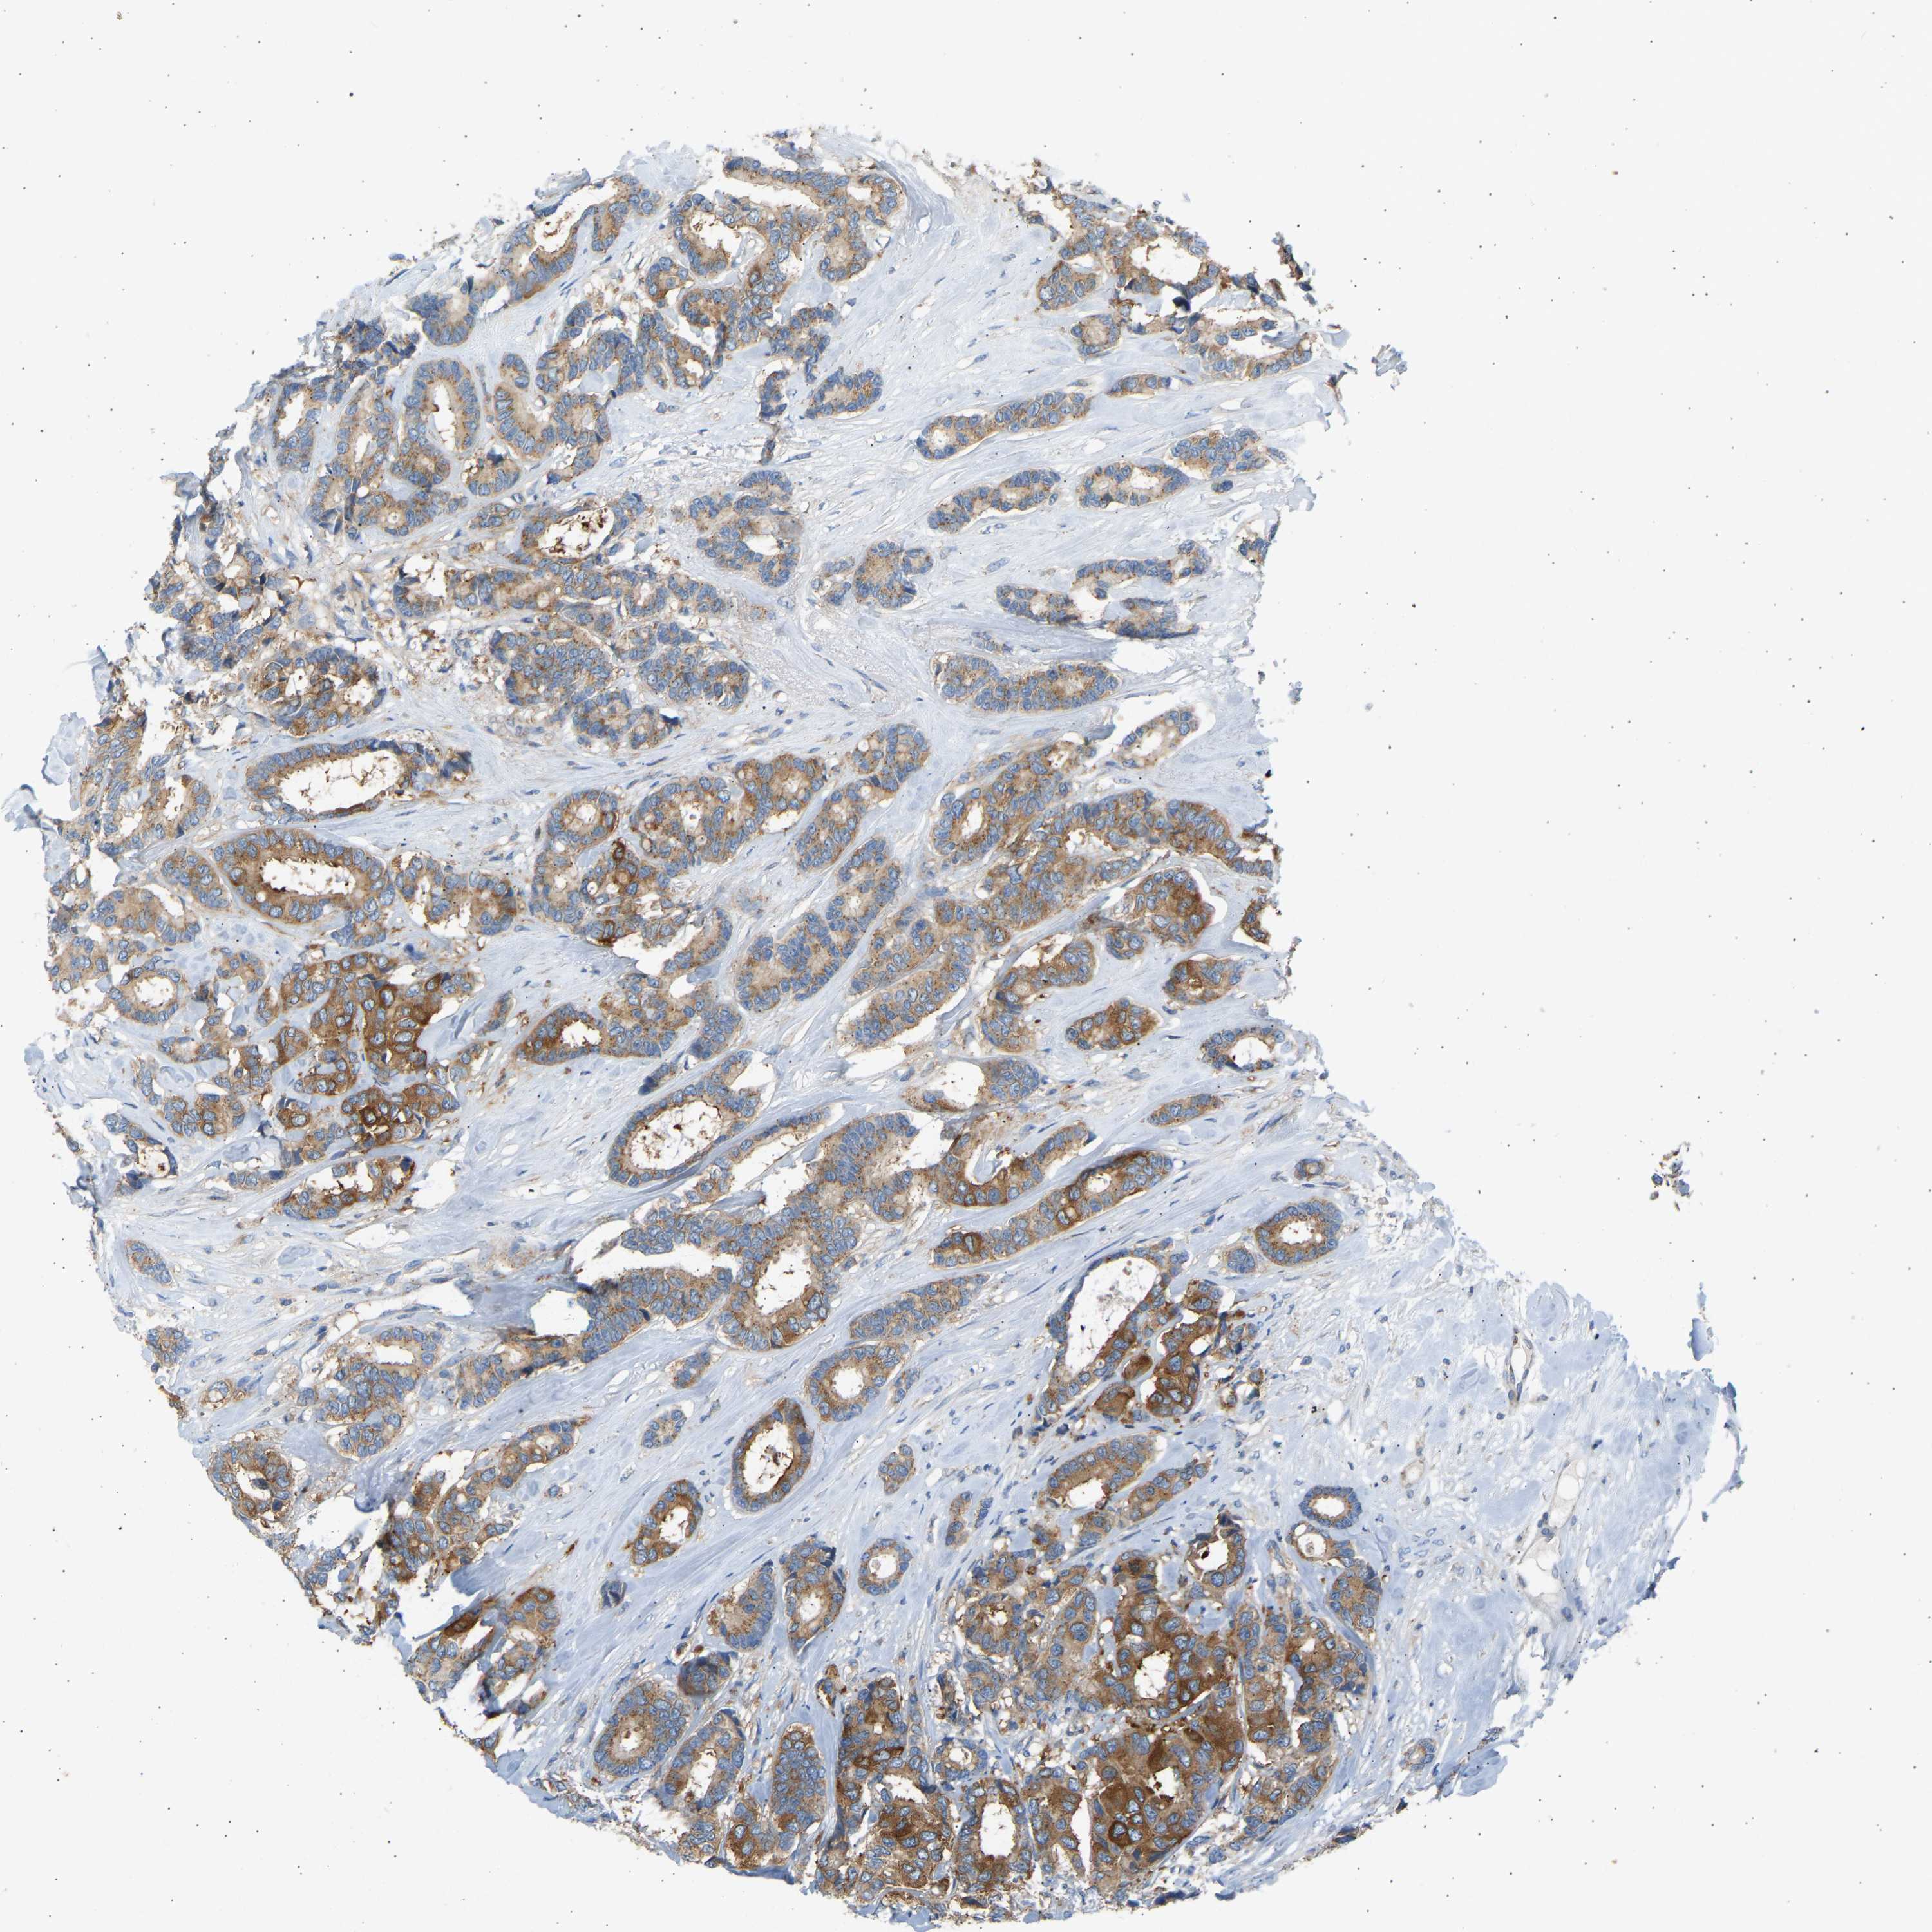

CANCER BREAST CANCER Show tissue menu

BRCA TCGA BRCA VALIDATION PROTEIN EXPRESSION

ANTIBODIES

AND

VALIDATION